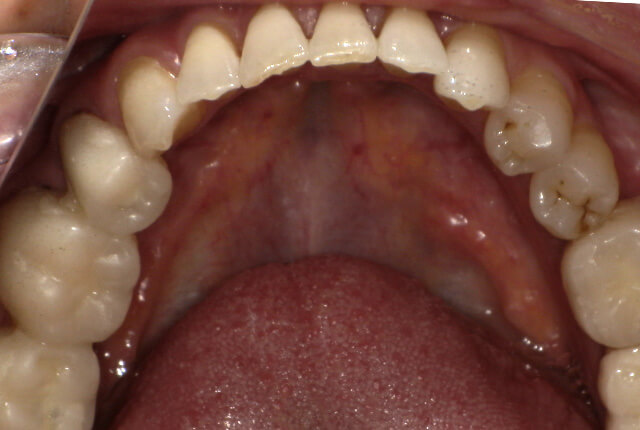

| 主訴 | 噛めない、食事がしっかりできる様になりたい。 |

| 診査診断 | 歯周病、歯の崩壊、不良補綴。 全顎的咬合異常、前歯の噛み合わせ、奥歯の噛み合わせに問題あり。 |

| 治療計画 | 欠損部インプラント 不良補綴のやり直しと欠損部インプラント。 咬合の再構築、なるべく歯を残せる様に治療計画を立案。 |

| 治療期間 | 6ヶ月 |

| 費用 | 290万円 |

| リスク | 一般的なインプラントのリスク、抜歯のリスク |